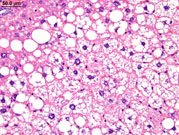

Periportal fatty change. The large, sharply delineated, clear vacuoles represent fat that has been dissolved during tissue processing. Deposition of fat in the hepatocyte cytoplasm often displaces the hepatocyte nucleus to the periphery of the cell.